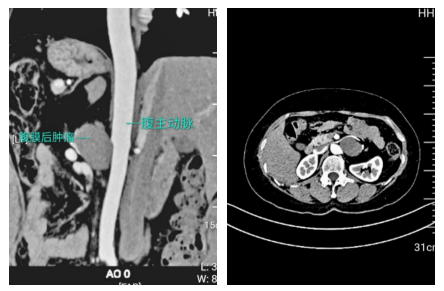

入院后,李广恩教授团队立即为王女士完善了腹主动脉CT造影(CTA)和上腹部增强CT检查,检查结果显示:腹膜后肿瘤与左肾血管分界不清,且紧邻胰腺、脾脏、腹主动脉等重要结构;更棘手的是,肠系膜上动脉存在“夹层”——血管内膜撕裂形成的假腔,如同在“生命管道”上凿出了一道裂痕,一旦术中操作不慎,可能引发大出血或肠缺血坏死。

李广恩教授介绍道:患者的肿瘤位于左肾动静脉之间,这些组织像“胶水”一样粘在本就菲薄的左肾静脉上,稍有不慎就会造成难以控制的汹涌出血,既要保证肿瘤“整块切除”,又要保留左肾静脉及肠系膜上动脉的完整性,避免夹层破裂以及切除左肾,只能一点点轻柔分离。